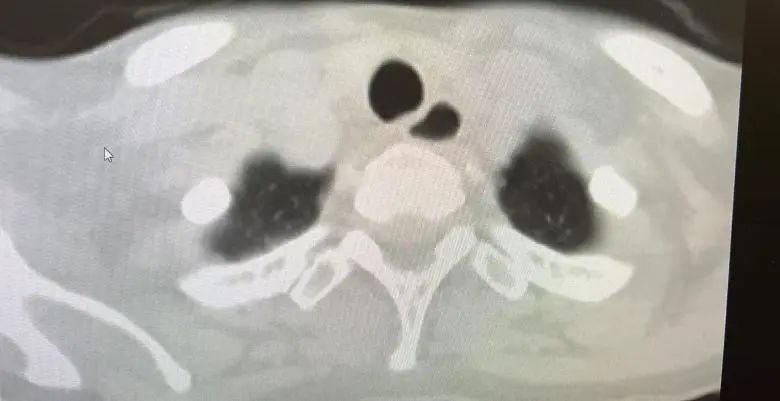

接诊时,李女士的情景很是危险。风湿免疫科主任庄宇、张雪珍副主任医师经详备问诊和针对性查验后,马上捕捉到重要信息:肌肉无力致行走艰难、吞咽艰难激发呛咳、呼吸艰难领导肺部受累;血液检测中,肌酸激酶(CK)高达 14314 U/L,远超浅显值百倍;勾通特异性抗体(抗 SRP 抗体)阳性等成果,会诊指向了不吉的免疫介导坏死性肌病(IMNM)——这是一种进展迅猛、可累及呼吸、吞咽及心肌的危重自己免疫性疾病。

李女士所患的免疫介导坏死性肌病(IMNM),属于特发性炎性肌病的亚型,是一种冷漠的自己免疫性肌肉疾病,会因不同类型抗体而有不同的临床推崇,主要以亚急性近端肢体肌无力和血清肌酸激酶(CK)显赫升高为特征,肌肉无力进展迅猛且严重,常快速涉及算作、吞咽及呼吸功能。其中枢计制是免疫系统很是报复肌肉组织,导致肌肉毁伤。